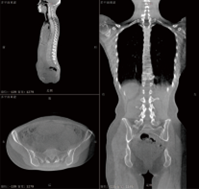

MPR (Mehrfache planare Rekonstruktion)

Die MPR „Multiple Planar Rekonstruktion“ ist eine einzigartige Methode der 3D-Bilddiagnose, die übersehene Beobachtung realisieren kann; Diagnose und Messung der 3DDaten des Patienten durch die koronale Ebene, die sagittale Ebene und die transversale Ebene.